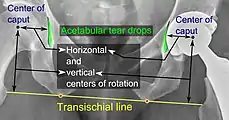

Center of rotation: The horizontal center of rotation is calculated as the distance between the acetabular teardrop and the center of the head (or caput) of the prosthesis and/or the native femoral head on the contralateral side.[80] The vertical center of rotation instead uses the transischial line for reference.[80] The parameter should be equal on both sides.[80]

Center of rotation: The horizontal center of rotation is calculated as the distance between the acetabular teardrop and the center of the head (or caput) of the prosthesis and/or the native femoral head on the contralateral side.[80] The vertical center of rotation instead uses the transischial line for reference.[80] The parameter should be equal on both sides.[80]